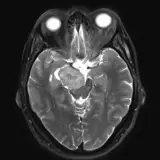

Neuro MRI